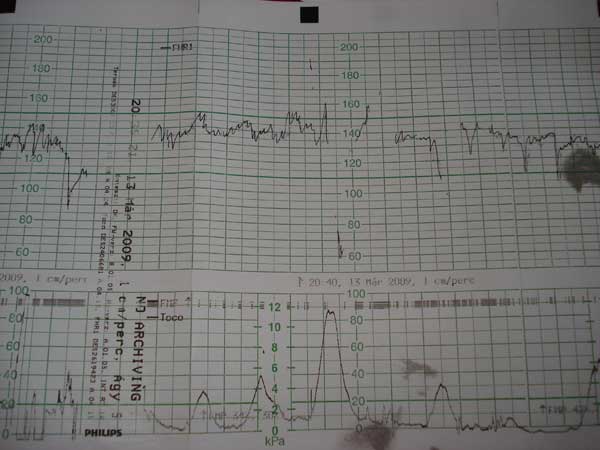

Annus, hoogy megnyugodj, engem ezzel a ctg eredménnyel igaz benn akartak tartani, de csak hogy hátha segítene egy kis magnézium infúzió. Akkor kérdeztem, hogy aki 34 hetesen ilyet produkál, azt hazaengedik? Mondták, hogy igen, na én akkor hívtam a párom, hogy jöhet értem. Szóval, nekem volt egy nagyobb összehúzódás, amit látsz, meg kisebbek alul. De az igazi fájás 120-tól van, azt mondta a szülésznő. (Tudod, ez akkor készült, mikor légszomjjal vebevittek, és több órán át rajtam volt a kütyü, fekvő helyzetben.